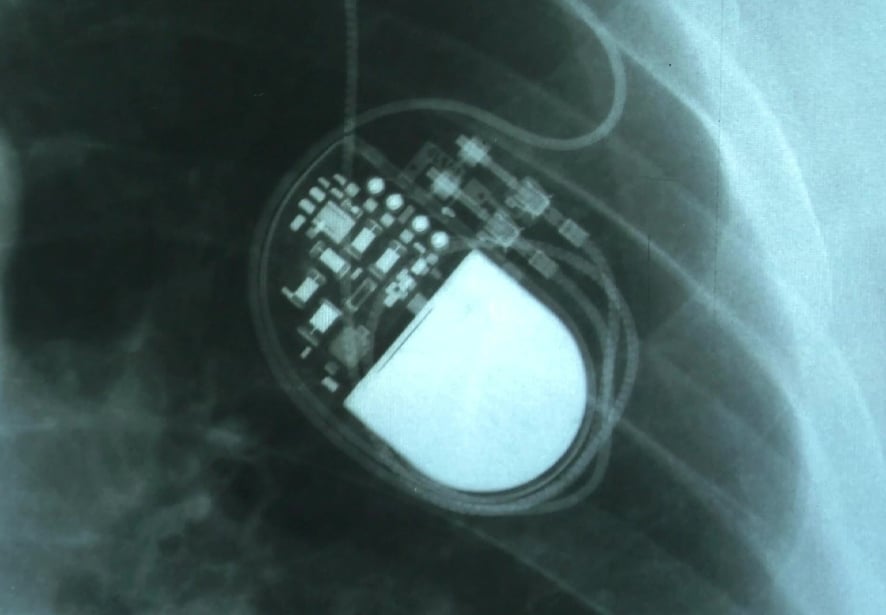

Pacemakers

A pacemaker is a medical device that monitors and regulates heart rhythms. It delivers electrical impulses right to the heart to maintain a regular heartbeat and help reduce symptoms of AFib.